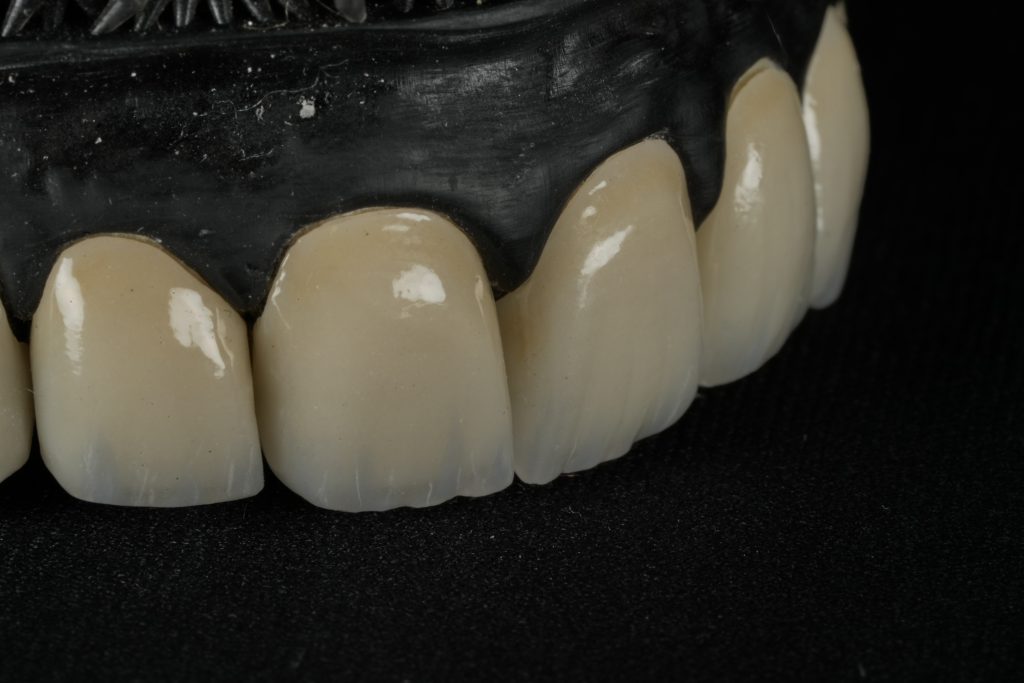

IPS E-max Press veneers were pressed and characterized using micro-layered incisal ceramics for vitality and translucency. Surface texture and internal effects were customized to simulate natural perikymata and halo zones (Fig 3).